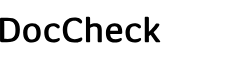

EDAN Échographe DUS 60

Échographe DUS 60 de EDAN

L'échographe DUS 60 de Edan convainc par une qualité d'image optimisée. En outre, le système d'échographie est facile à transporter et peut donc être utilisé à différents endroits. La technologie entièrement numérique de cet appareil permet de voir et d'évaluer les détails les plus infimes. Le clavier de l’échographe DUS 60 est équipé d'un rétroéclairage, ce qui rend l'échographie plus conviviale pour le patient, car l'appareil peut également être utilisé dans une salle d'examen sombre. Les résultats de la fonction Doppler et les images échographiques obtenues sont faciles à interpréter grâce à la fonction multi-pseudo-couleurs.

- Appareil d'échographie mobile avec écran LCD et sonde

- Moniteur 12,1" avec 256 niveaux de gris et fonction multi-pseudo-couleurs

- Disposition du clavier : QWERTY